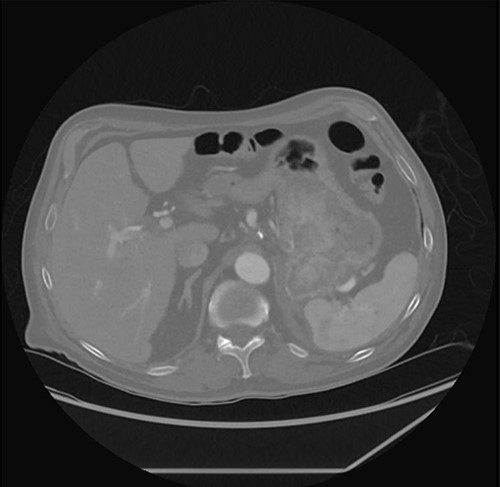

Prior to his scheduled surgery he presented to the emergency department in December 2021 with complaints of dizziness and syncope. Initial examination showed tachycardia and orthostatic hypotension consistent with hypovolemia. Cardiopulmonary and abdominal exams were unremarkable. Laboratory data were significant for a hemoglobin of 7.5. He was admitted and treated with intravenous fluids and two units of pRBCs. A computed tomography (CT) abdomen/pelvis done on admission showed the stomach mass similar to the previous scan done four months prior (Fig. 2).